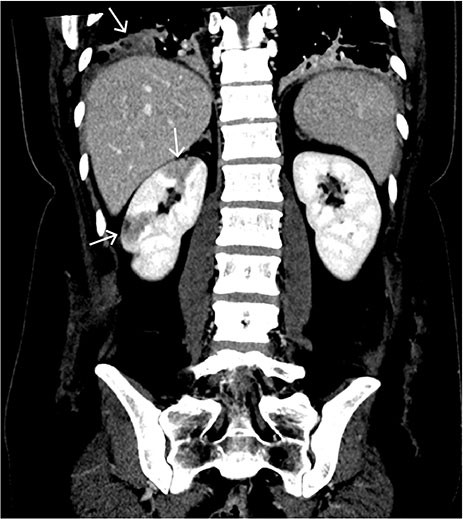

The abdominal CT with intravenous contrast showed well-demarcated, peripheral, wedge-shaped hypodense areas in the right kidney, most consistent with recent renal infarction (Figure 2). No bleeding or other relevant pathology was observed in the abdomen.

Hypodense lesions in the renal parenchyma can be seen in hypoperfusion and are mostly caused by acute renal infarction or pyelonephritis. Due to the well-demarcated peripheral, wedge-shaped lesions and absence of reaction in the perirenal adipose tissue, the findings are most consistent with renal infarction. This is a rare condition in which complete or partial occlusion of the renal artery or its branches causes ischemia in the kidney. Renal infarction can present with flank pain, nausea, fever and haematuria (3). However, the clinical picture can be subtle and the diagnosis can be missed. The condition can be complicated by reduced glomerular filtration and kidney failure.